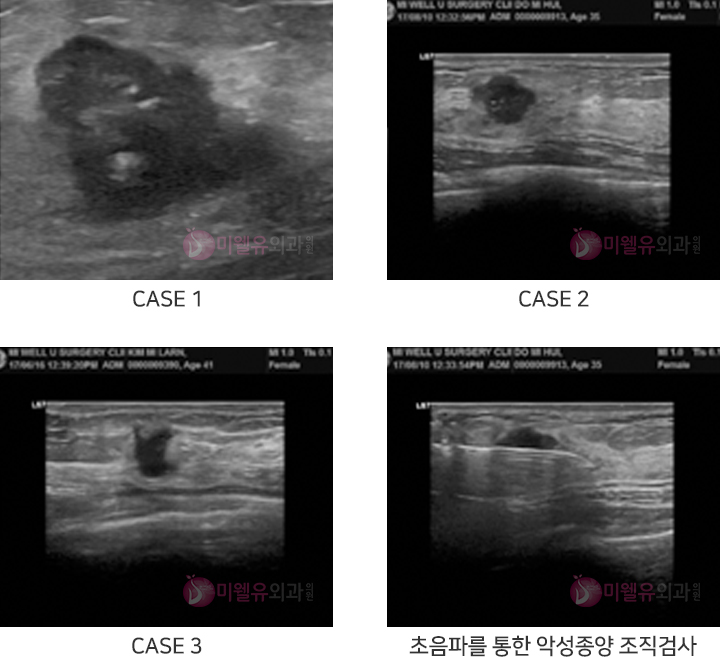

초음파 장비는 인체에 무해한 초음파를 이용하여 인체의 조직 단면을 영상화 시켜 진단하는 장비로

성능은 가격에 따라 천차만별이며 검사자의 능력에 따라 결과의 차이가 있는 장비입니다.

유방암 갑상선암

등의 검진

유방의 양성종양,

악성종양, 염증성 병변 등

영상소견 진단 및 경과

다양한 병변의 상태

및 경과 진단